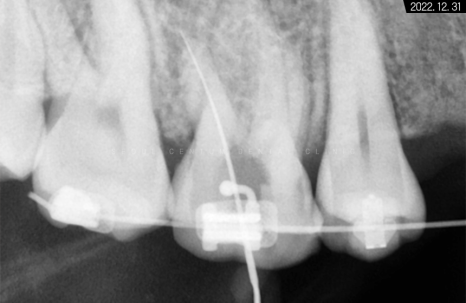

이 같은 미니스크류를

치아 상실된 부위에 식립하였습니다.

와이어에 파워체인을 연결해서 당기면

힘도 잘 받고 원하는 방향으로

움직이기에 용이해져서

더 좋은 결과를 만들 수 있습니다.

환자분께서는 치성, 잇몸 전돌 양상이

심한 편이셨기 때문에

양쪽에 미니스크류를 심고

파워체인을 걸어 조금 더 힘을 주었습니다.

빈자리에 고정원이 잘 심어진 것이 보이시죠?

아직은 기대 이상의 결과물이 나온 상태는 아니지만

브라켓도 떨어지지 않고 잘 유지되고 있어

지켜보기로 했습니다.